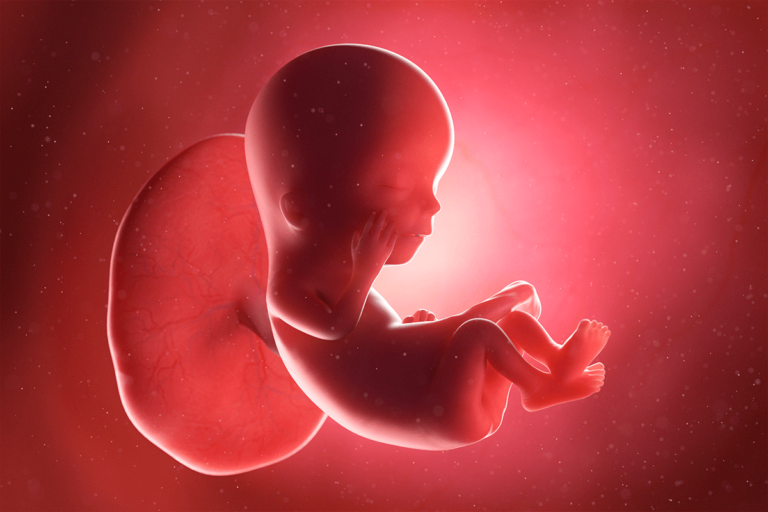

Es la semana 12 del embarazo y se acerca el final del primer trimestre. Tu bebé ha crecido mucho. Ahora mide entre 5 y 6 centímetros y pesa entre 8 y 14 gramos.

Puede que apenas se note la barriga, pero tanto el bebé como tú han estado trabajando en el crecimiento y el desarrollo. El feto ya ha aumentado más del doble de su largo en las últimas 3 semanas y tiene el tamaño de una lima.

El proceso de desarrollar nuevas estructuras también está llegando a su fin, por lo que comienza la etapa de maduración. Esto significa que se avecina un proceso de crecimiento de los órganos que ya están casi completos, como los intestinos y los riñones.

Así mismo, aparecen los primeros reflejos. Un reflejo es una respuesta automática del cuerpo a un estímulo. En este caso, los dedos del bebé se abren y se cierran, los dedos de los pies se curvan, los músculos se tensan y la boca comienza a hacer movimientos de succión.

Por su parte, el sistema digestivo fetal se está preparando y ha puesto en práctica los movimientos de contracción que necesitará, luego de nacer, para empujar los alimentos a través del tracto digestivo. Esto es lo que se conoce como peristaltismo.

En el caso de la médula ósea, la misma ya se encuentra produciendo glóbulos blancos, los que permitirán que tu bebé esté preparado contra posibles infecciones después del nacimiento. Al mismo tiempo, tu sistema inmune está aportando a sus barreras defensivas, de manera que puedas protegerlo de antemano.